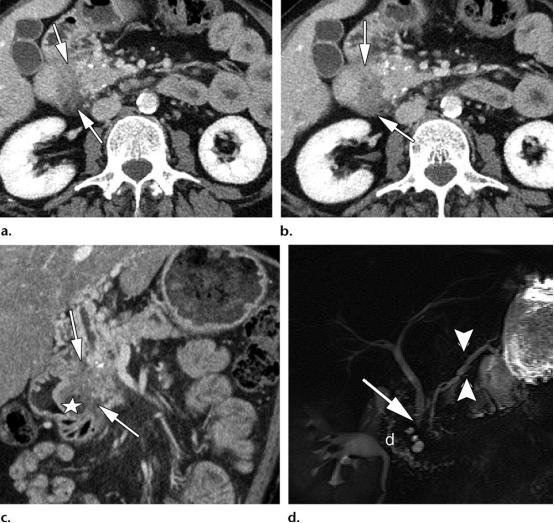

39岁男性,1型实性十二指肠旁胰腺炎(PDP,即沟槽性胰腺炎)

(a图,b图)轴位CT示边界不清的低密度肿物样病变,位于十二指肠胰腺沟内(白色长箭头),胰头区可见散在的胰腺实质钙化灶。

(c图)冠状位CT图示十二指肠沟内肿物样病变(白色长箭头),以及十二指肠壁的囊性变(白色五角星),胆总管远端部分可见。

(d图)磁共振胆胰管成像示胆总管远端局灶狭窄(白色长箭头),胰腺分支胰管略微显著(白色短箭头),注意观察十二指肠胰腺沟的增宽,以及十二指肠壁的囊性变(白色字母d)。